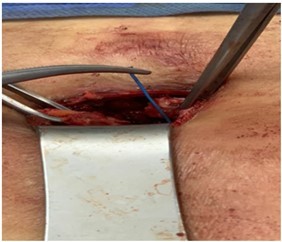

d) Excision of the track we usually find the offending wire(s) at the base of the track (Figure 2)

Figure 2.One of the offending pacing wires found adjacent to back of the xyphoid process. It is held with forceps.